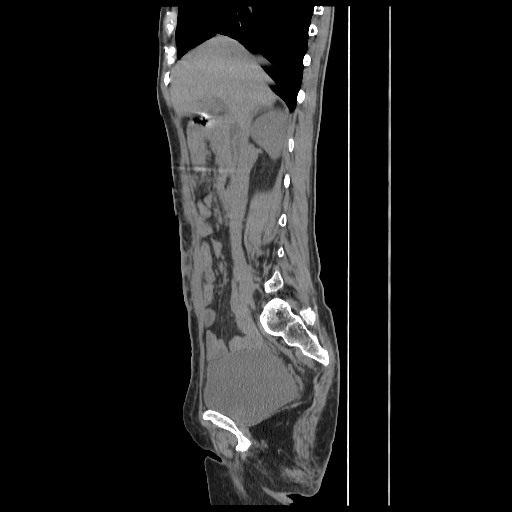

Radiological images:

CT-Scan investigation done on 16Apr16